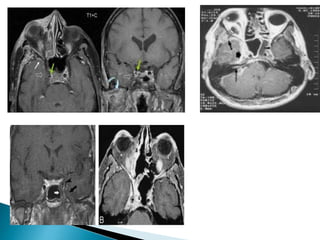

3) MRI:

๏ฝ โ€“ A sensitive, noninvasive

๏ฝ Can be combined with venography to

demonstrate lack of blood flow in the

cavernous sinus

๏ฝ Show associated meningitis, involvement of

pituitary gland

3) MRI: ๏ฝ โ€“A sensitive, noninvasive ๏ฝ Can be combined with venography to demonstrate lack of blood flow in the cavernous sinus ๏ฝ Show associated meningitis, involvement of pituitary gland